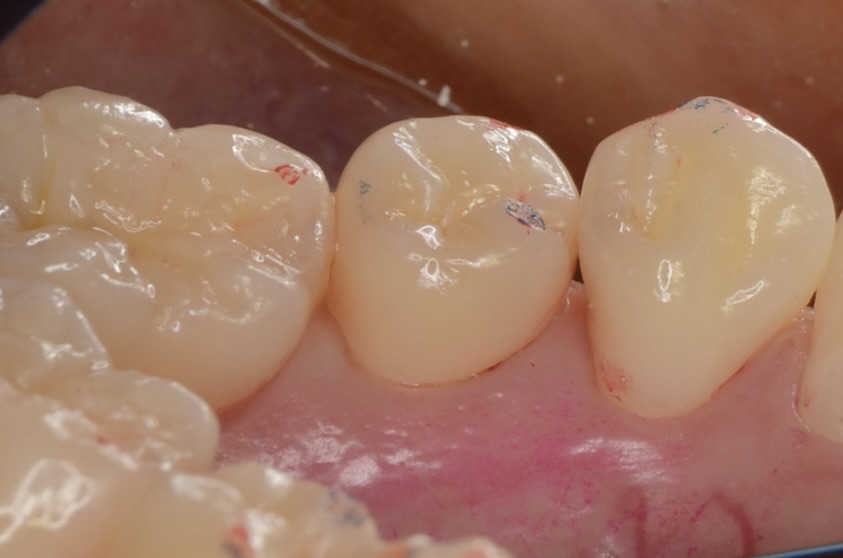

After

レジン充填完了

フロスを通してみて適切な、きつさがあるのを確認しています。 -

咬合面から見る

このように歯並びが若干乱れている場合の、歯と歯の間にできた虫歯治療は意外と難易度が高いです。しかしセパレーターを使って歯間離開させ、フロワブルレジンの表面張力を利用して充填すれば、滑らかで、引っ掛かりのない歯の形態を再現できます。